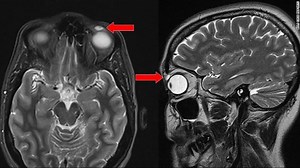

Woman’s painful cyst turns out to be contact lens embedded in eyeli